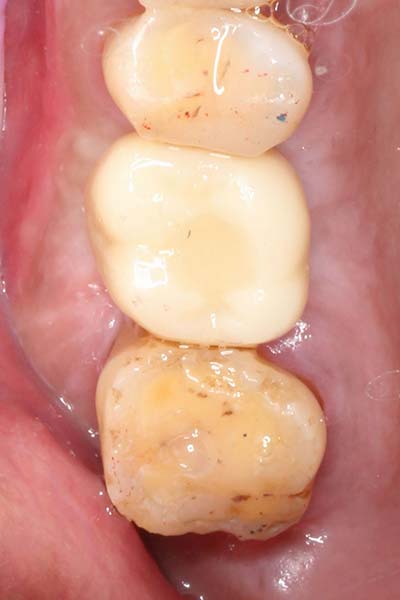

微創植牙 首頁 案例分享 人工植牙 微創植牙 微創植牙 牙周病的牙齒,因為骨頭破壞,只好拔除 拔牙後,置入骨粉,靜待骨頭癒合 晴美牙醫擁有豐富竹北微創植牙經驗,欲瞭解更多相關知識,可至診療項目-微創植牙頁面。 傷口癒合良好 微創不翻瓣 置入植牙 裝置假牙